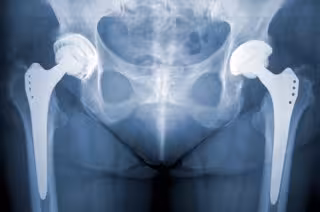

Reducir el consumo de tabaco y alcohol disminuye el número de fracturas de cader

Reducir el consumo de tabaco y alcohol disminuye el número de fracturas de cader - GETTY IMAGES/ISTOCKPHOTO / NORBERT - Archivo